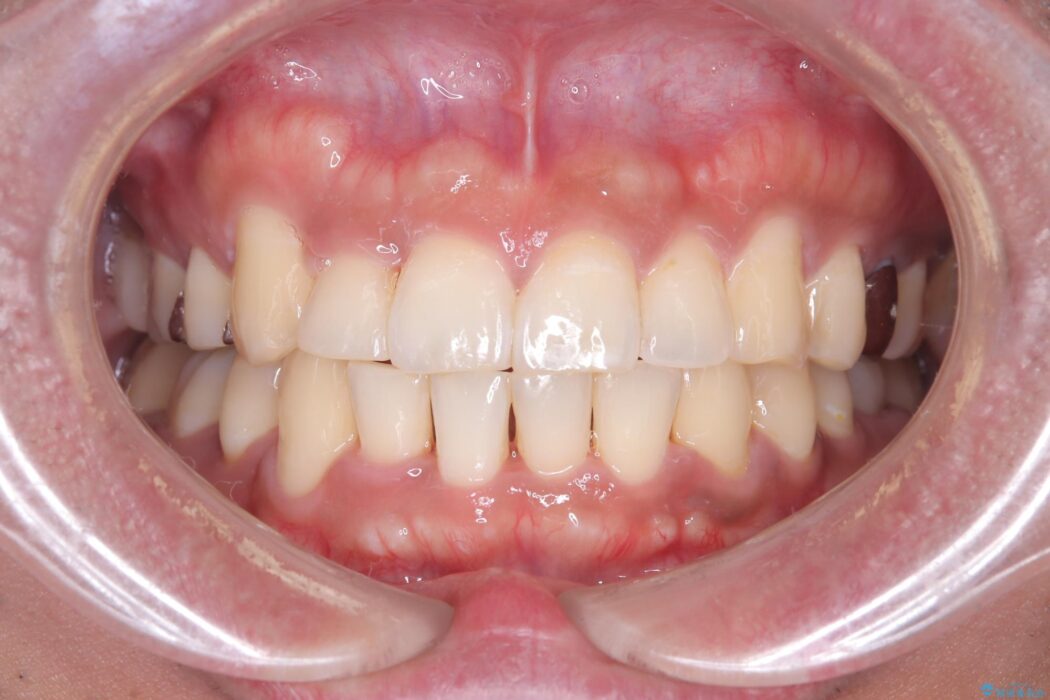

噛み合わせのズレが右側で大きかった(2級)ため、右側上下2本の歯を抜歯し、ワイヤー矯正で噛み合わせを左右対称の理想的な位置に改善しました。

気になっていた八重歯や凸凹が改善され、大変ご満足いただけました。